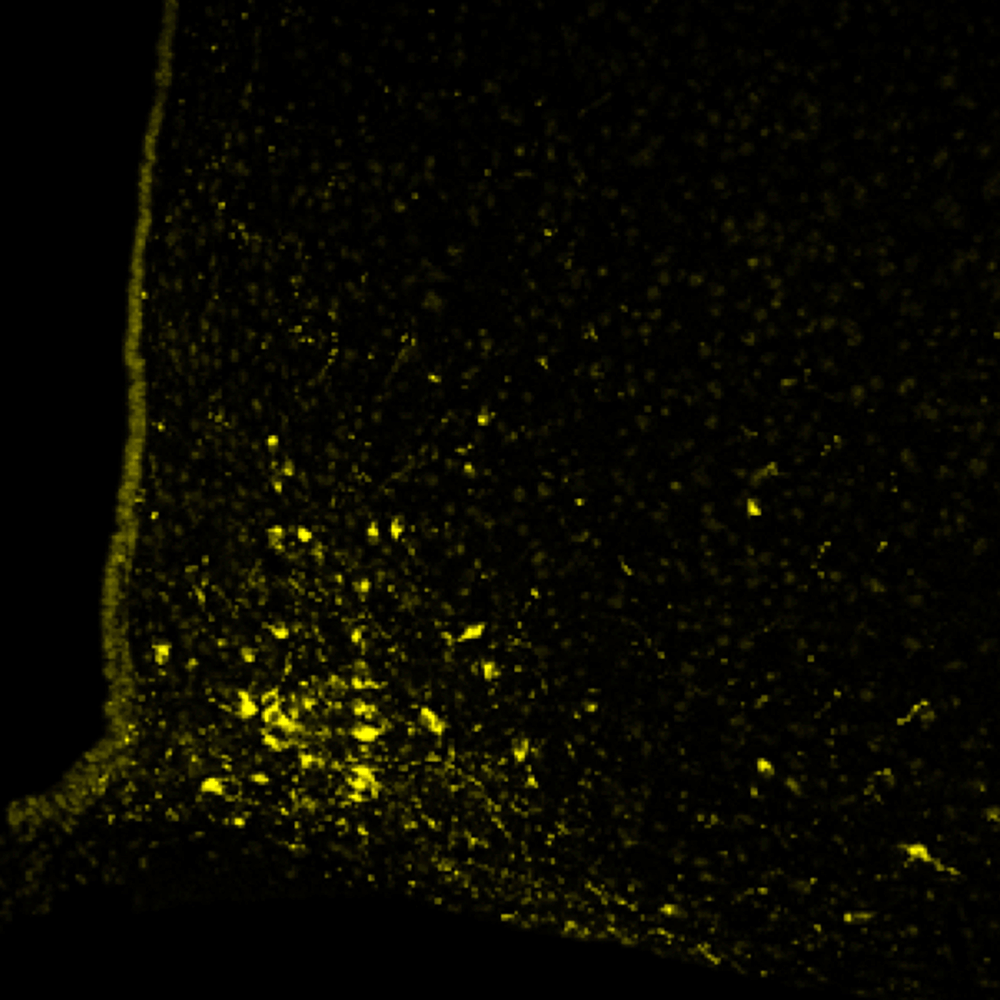

Our research shows that overfeeding in early life can contribute to central inflammation that may permanently influence hypothalamic feeding and stress circuitry; leading to an increased propensity to gain weight and stay fat, hyperactive responses to stress, infertility, and an inability to appropriately respond to inflammatory challenges.

We have a particular focus on the role of microglia in these effects and are also establishing microglia’s role in healthy brain function, including appetite and cognition.